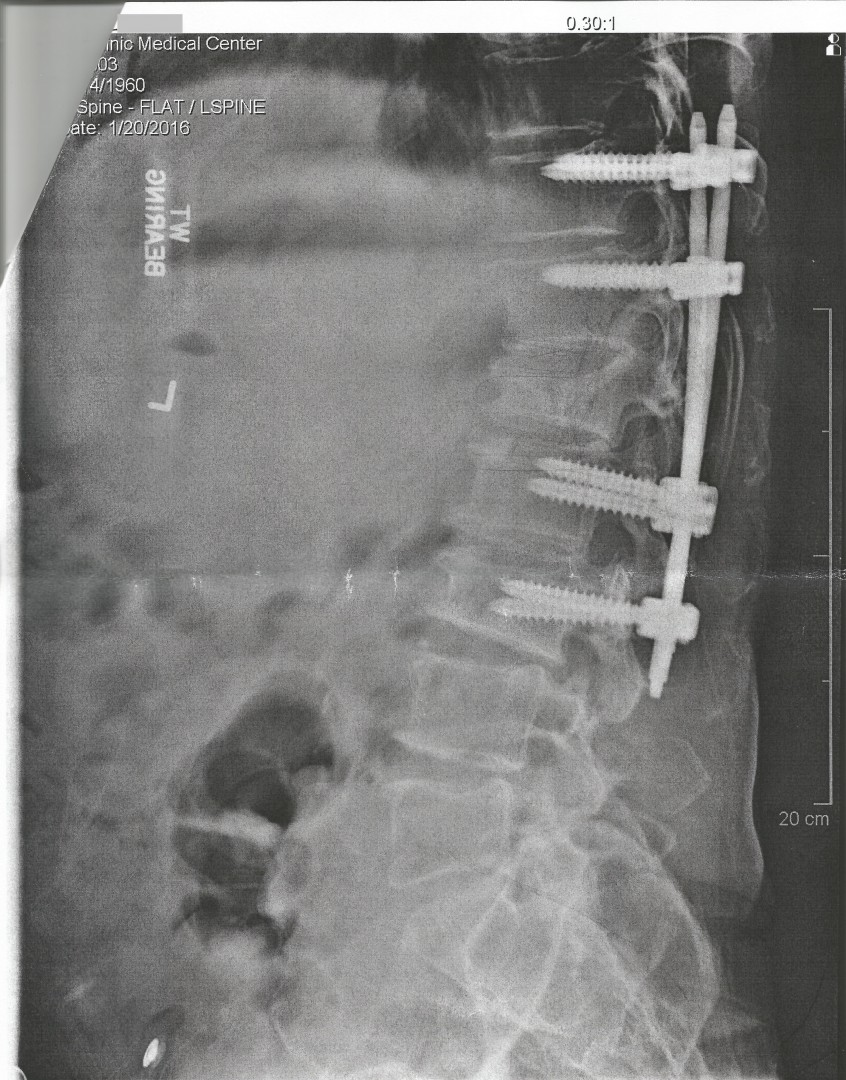

Wow Mike, That really looks BAD! And you say that doesn't hurt? Your one though guy!! I hope you can get some relief on the compression in your spine. That's a lot of hardware in that there X-RAY. You must be on the NO FLY LIST- Your not getting through TSA at the air-port with that! RC

Lol. You are so right. I've been to Home Depot a million times in my life and I see no difference between the hardware I bought there and the hardware they put in my back (image attached). And all the money I spent at Home Depot all these years is a very tiny fraction of what they charged my insurance company for the 8 lag bolts and 2 rods that they put in my back. The good news is that it doesn't cause me any pain - just makes me move like a 'stick-man' Lol. The bad news is that I have an untreated L4-L5 disc extrusion that is compressing the L5 nerve root. I refuse to take pain medication in an attempt to preserve my cirrhotic liver but it's getting to the point that I'm considering letting my surgeon do an epidural or spinal block. This pain wasn't as bad when I was on treatment but I doubt that there is any relation. I did however have more arthritis pain in my joints and in some old traumatic injury sites when I was on treatment which did subside slowly after EOT.